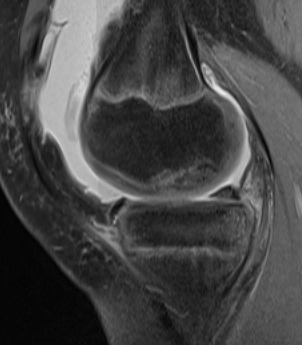

MRI Classification

Stage 1: Low signal changes, articular cartilage intact (stable)

Stage 2: Articular cartilage breached, low signal indicating fibrocartilage behind fragment (stable)

Stage 3: Articular cartilage breached, high signal indicating synovial fluid behind fragment (unstable)

Stage 4: Loose body (unstable)

Look for

- integrity of the articular cartilage

- fluid behind the lesion, suggesting instability

- displacement of the lesion

Stable

- no synovial fluid behind lesion

Unstable

- cartilage breach with synovial fluid behind lesion

Stage 1. Articular cartilage intact

Stage 2. Articular cartilage breach, but low signal intensity behind fragment

Stage 3. Articular cartilage breach and synovial fluid behind fragment (unstable)

Stage 4. Loose body